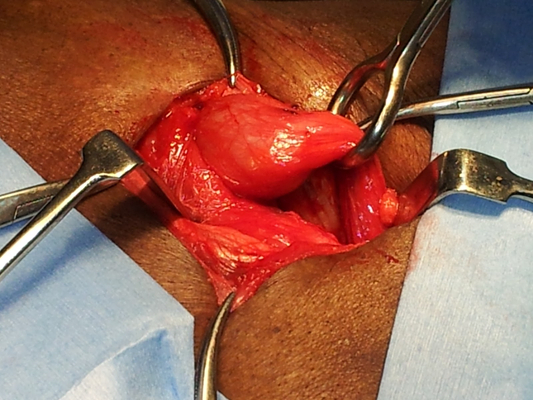

顱內血腫圖片

硬膜下血腫 (7)

硬膜下血腫 (8)

硬膜下血腫 (9)